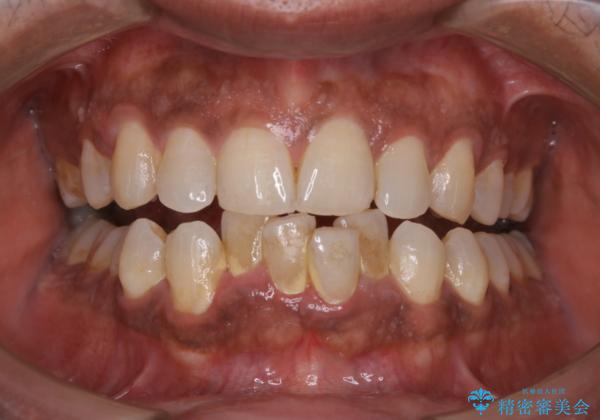

ステインとプラークが内側外側にとても多く付いていました。

タバコも吸うそうで、ステインが多かったです。60分コースでもギリギリ終わるくらいの汚れの量だったため、定期的にクリーニングやメンテナンスを行うようにおすすめしました。